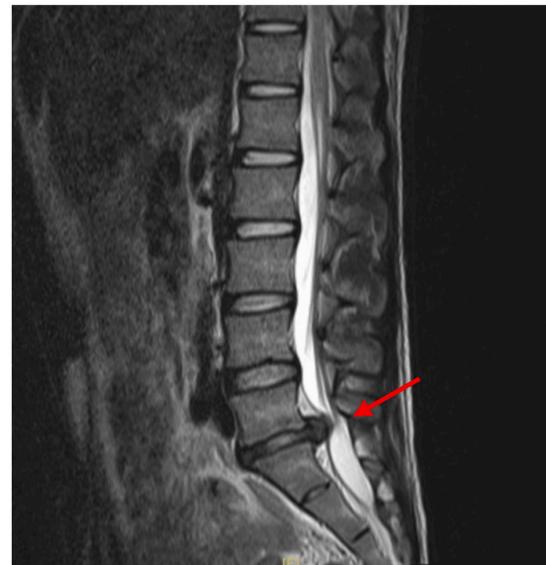

Cauda Equina Syndrome Z

- Etiology: Severe compression of nerve roots in the thecal sac of lumbar spine, most commonly due to acute lumbar disc herniation

- Critical: Early diagnosis is essential

Clinical Features:

- Back pain (most common)

- Unilateral or bilateral leg pain (2nd most common)

- Saddle anesthesia (highly specific)

- Bladder dysfunction: Urinary retention → overflow incontinence

- Unilateral or bilateral sensory changes in legs

- Unilateral or bilateral motor weakness in legs

Diagnosis:

- Urgent MRI to confirm cause

Treatment:

- Prompt surgical decompression

- Should be performed within 24 hours, absolutely within 48 hours

Lumbar Disc Herniation

- Significance: Very common cause of low back pain and unilateral leg pain (radiculopathy)

- Diagnosis: Made clinically and confirmed with MRI studies of lumbar spine

- Initial treatment: Nonoperative with oral medications and physical therapy for radicular leg pain

- Surgical indication: Microdiscectomy for severe pain and/or motor deficit that have failed to respond to nonoperative management

L5/S1 Disc Herniation Example: